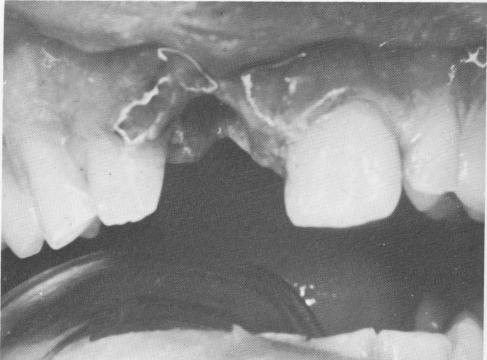

The crowns were cemented over the two protruding implant shafts in the same manner as in Case 1 (Fig. 8-14). However, whereas the implants in Case 1 were left completely unsplinted from the very onset, in this case the implants were immediately ligated to neighboring teeth with soft .010 stainless steel ligature wire (Fig. 8-15). The occlusion once again was carefully checked and all necessary adjustments were made (Fig. 8-16). A post-operative lateral plate roentgenogram of the completed case shows all implants in place (Fig. 8-17).